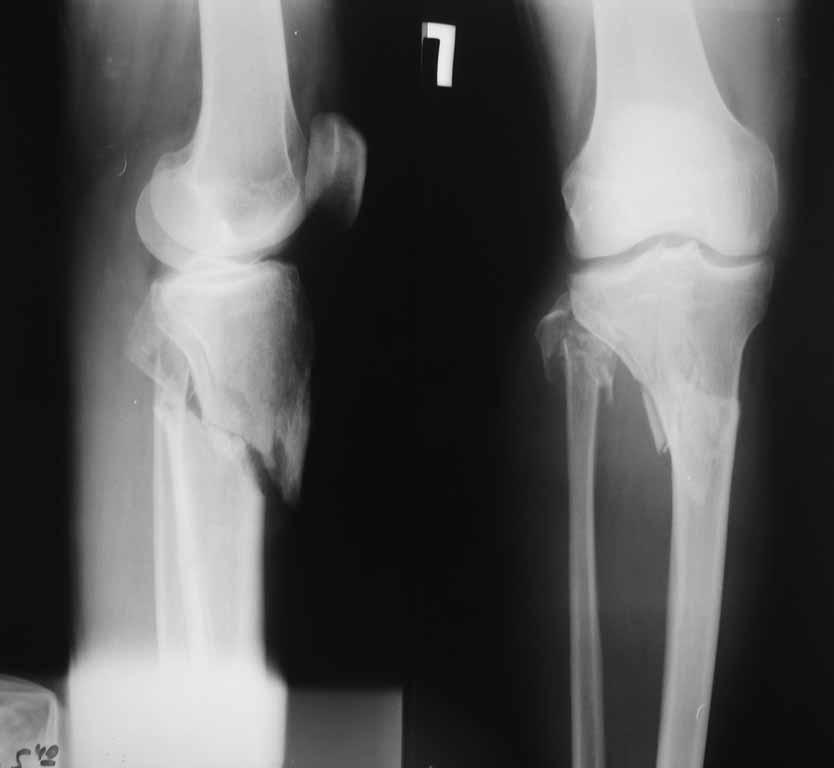

Подскажите пожалуйста, какой фиксатор подойдет для данного

перелома. Мужчина 40 лет получил закрытый внутрисуставной перелом верхней трети костей

правой голени в результате ДТП (см. рентгенограммы). Какой фиксатор подошел бы для данного

перелома понятно, однако у пациента имеется по передне-наружной поверхности верхней трети

голени ссадина и участок некроза кожных покровов (см. фото), поэтому латеральная

мыщелковая пластина не подойдет, а медиальных пластин у фирм-производителей нет. Пациент

может приобрести современный имплант, но какой….???? Слышал, что некоторые ставят,

например, левую латеральную мыщелковую пластину по медиальной поверхности правой голени –

работает ли это? Каким фиксатором и каких фирм прооперировали бы Вы??? Заранее СПАСИБО!!!